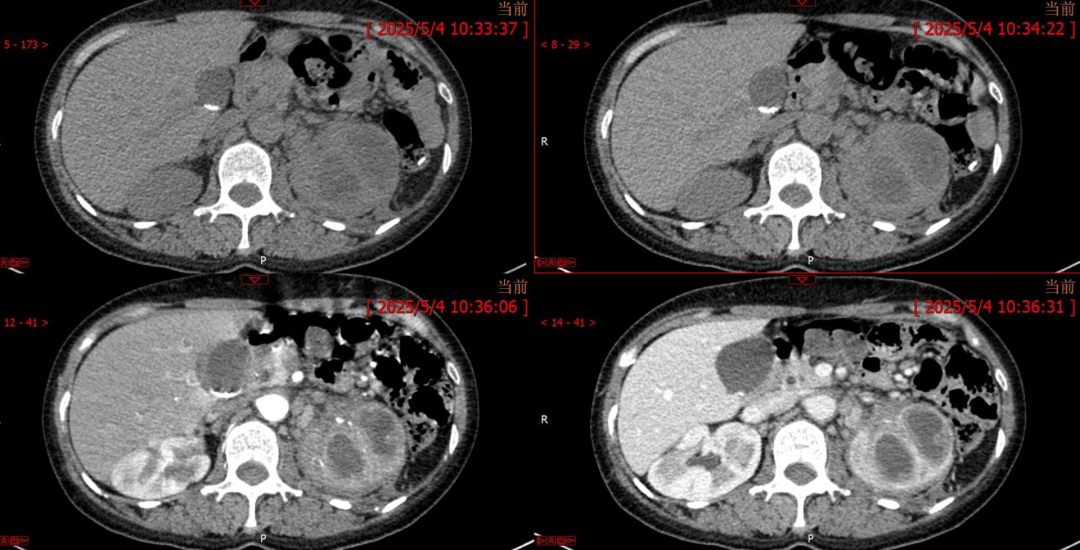

病例1女性,60岁主诉:反复左

病例2女,41岁,主 诉:体检发现右侧肾占位1天余。现 病 史:缘患者于1天因血压升高来我院就诊,体检发现右侧肾占位,

既 往 史:平素健康状况:良好,患者既往有高血压病史2年余,最高

影像表现为:右肾囊性肿块,肾周无软组织及渗出影,增强囊壁轻度强化,囊内弥散受限明显,不强化,周围有出血